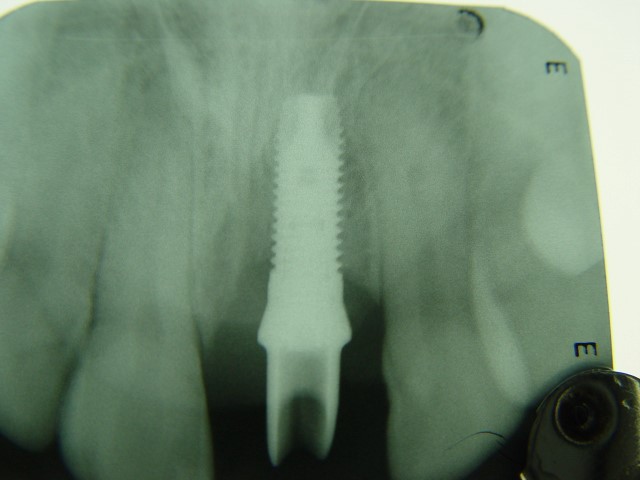

לאחר 3 חודשים מיום העקירה ביצוע צילום סיטי (טומוגרפיה ממוחשבת) לצורך תכנון ביצוע שתל בודד עם עיבוי העצם

ביצוע ההשתלה עם עיבוי העצם (אוגמנטציה)

צילום השתל עם המבנה לקראת השיקום